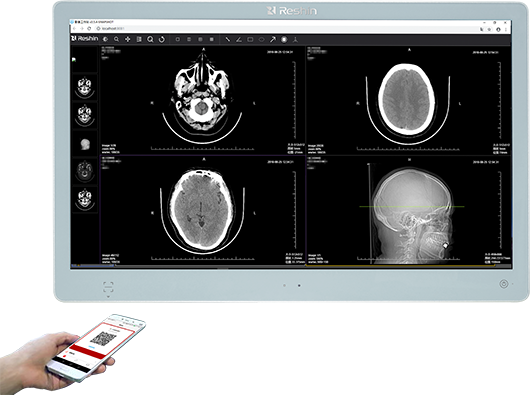

再者,稳定性与场景适配性的差异决定使用价值。远程会诊常需 7×24 小时不间断运行,医用显示器内置硬件校准模块,支持每月自动校准,面板和背光寿命达 10 万小时,且外壳采用抗菌材质、支持消毒剂擦拭,适配医院无菌环境;同时支持多屏联动、竖屏显示等功能,可直连 PACS 医学影像系统,提升远程会诊效率。普通显示器无校准要求,参数易漂移,且缺乏医疗场景专属设计,连续高负荷运行易出现闪屏、亮度衰减等问题。